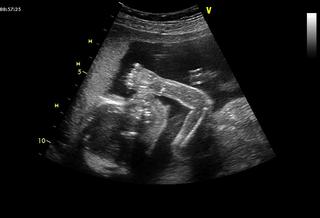

Ahoj, tak zase jsem na vysledek testu cekala az do druheho dne 😉 Ale dobry, jsem 19. den po ET bez PK a mam hCG 4165IU/ml, takze porad jsou ve hre dvojcata 😉 Na US jdu za 12 dni, to uz bude slysitelne i srdicko(ka), ktere by melo zacit bit dneska, jdu k Langerove, u ktere jsem zacinala a ktera me naposled videla, kdyz mi podruhe oddalovala stimulaci kvuli cyste 😉

@tereza1980 - tiež krásna foto 🙂 máte aj nožičky, narozdiel od nás 😉